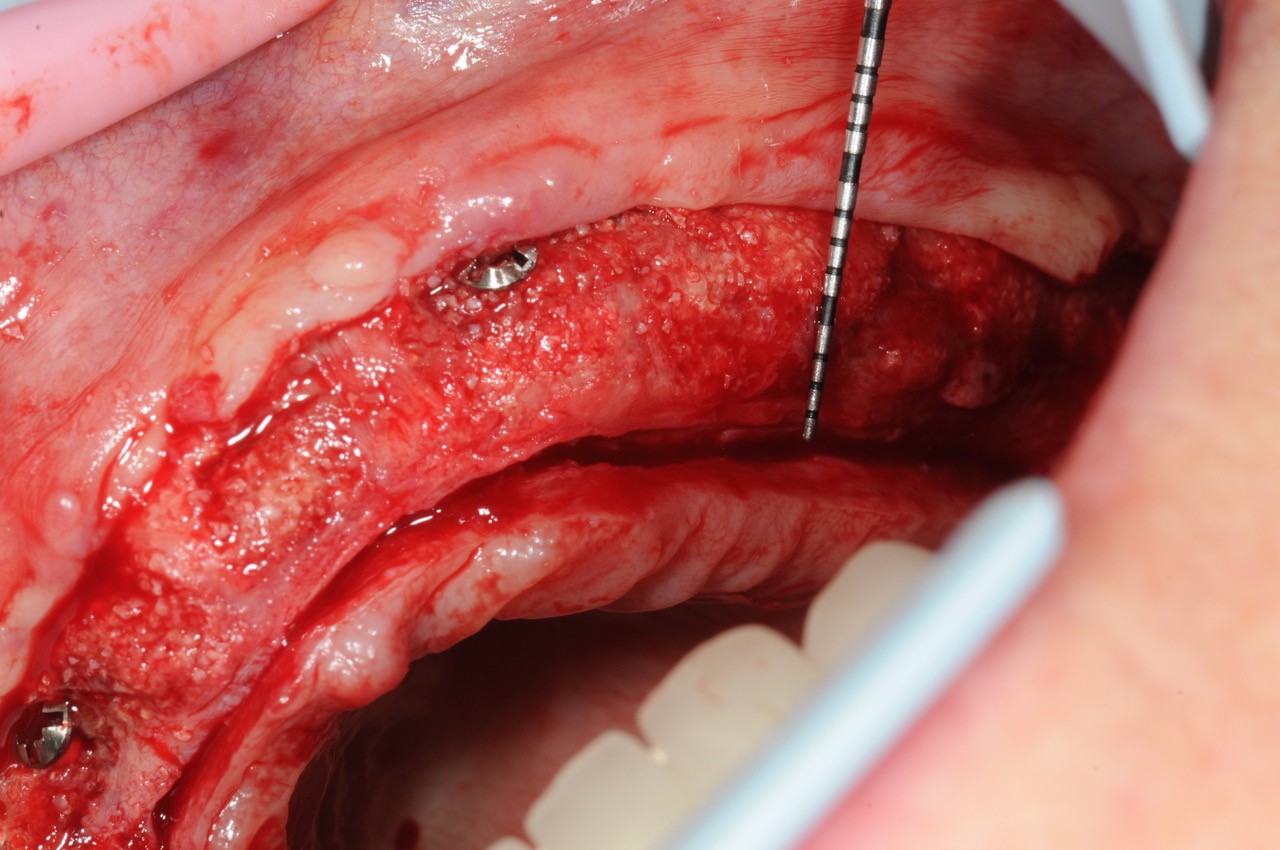

18/21 - 6 months post-op: situation at re-entry shows stable bone

19/21 - Stable bone with approx. 3 mm horizontal bone gain

20/21 - Stable bone with approx. 3 mm horizontal bone gain